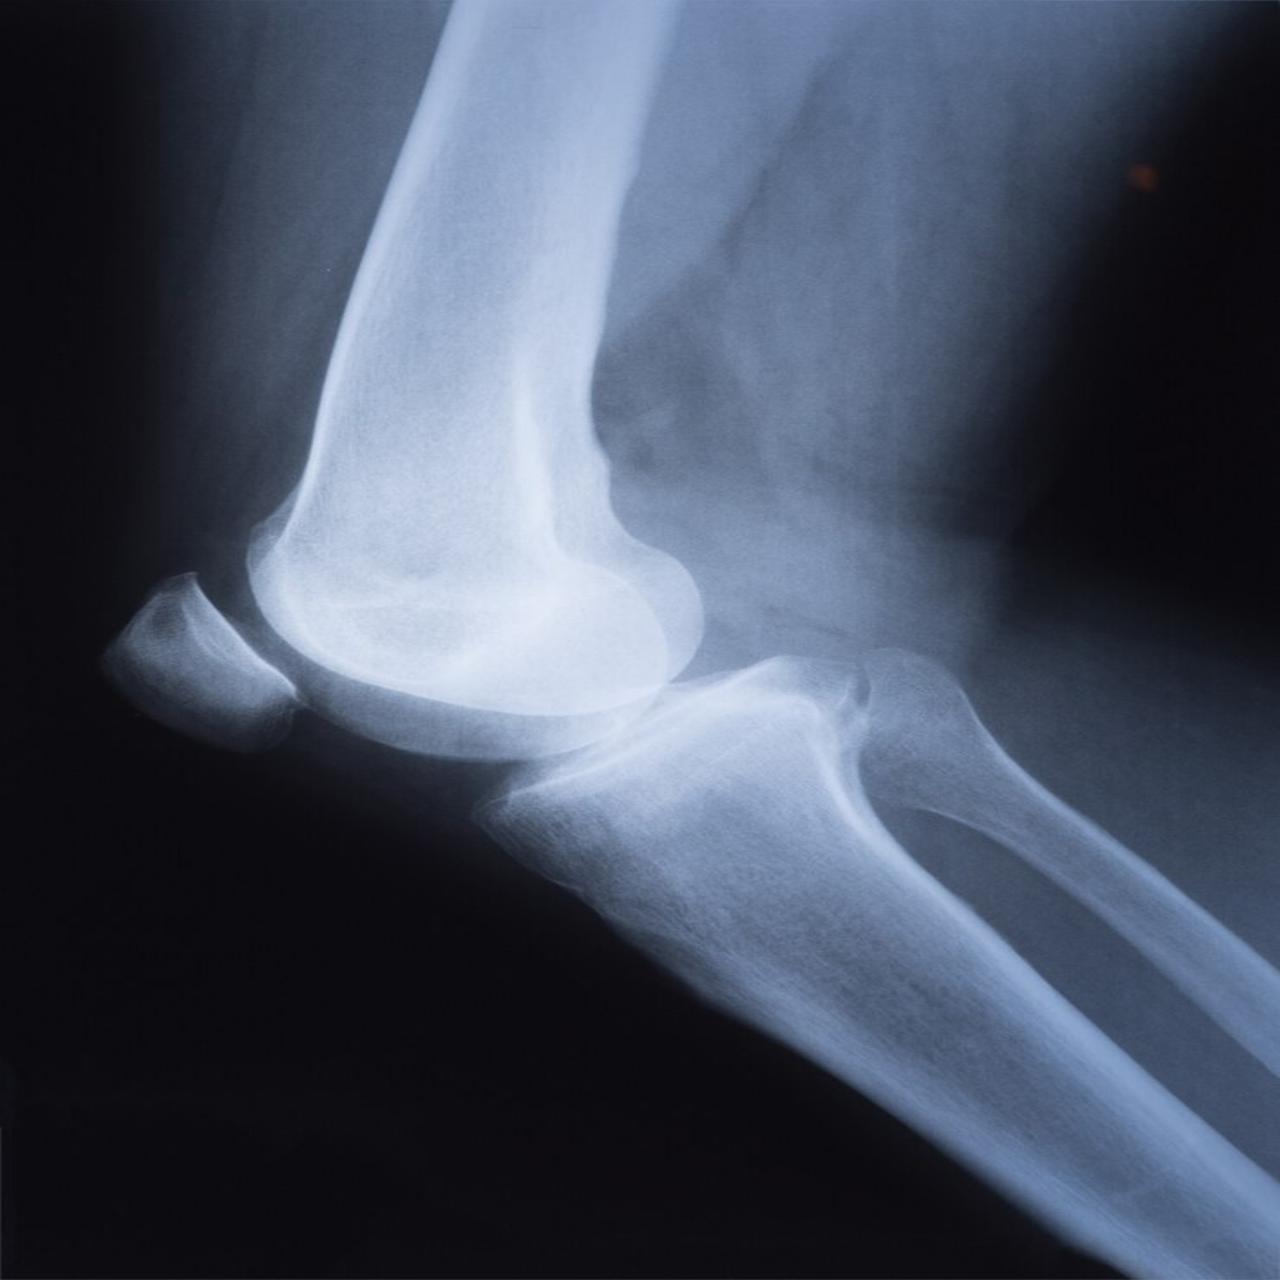

Knee X-ray is an imaging test used to view the bones of the knee joint. It helps detect fractures, arthritis, dislocations, or other knee problems.